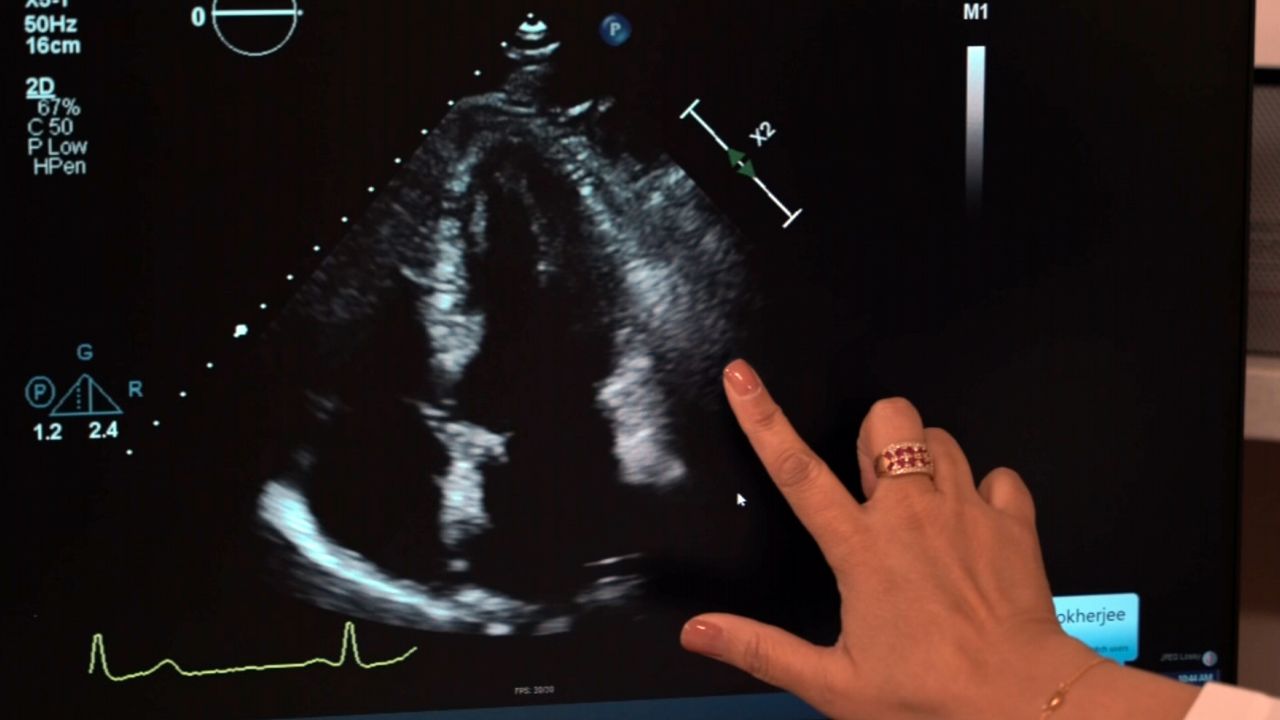

From ny1.com

Rare heart disease What you need to know What Is The Most Rare Heart Disease It causes the heart to have a harder time pumping blood to. 1 one person dies every 33 seconds from cardiovascular disease. Brugada syndrome is a rare inherited cardiovascular disorder characterized by disturbances affecting the electrical system of. Heart disease is the leading cause of death for men, women, and people of most racial and ethnic groups. Currently it is. What Is The Most Rare Heart Disease.